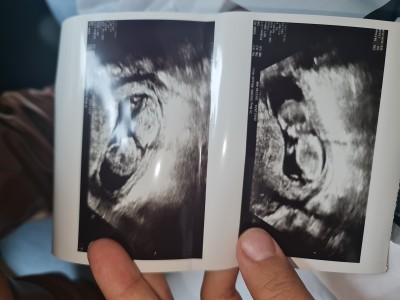

kızlar 12 haftaligim cinsiyet tahmini yapabilir misiniz lutfen

Gubu kiz cnm doktor torum yaptimi

Evet kemik yapisi kiza benziyor dedi ama şimdiden belli olmaz dedi

Erkeğe benzettim. Hayırlısı olsun :)

erkek gibi oyle gecti icimden

Kız gibi geldi

Bence erkek gibi